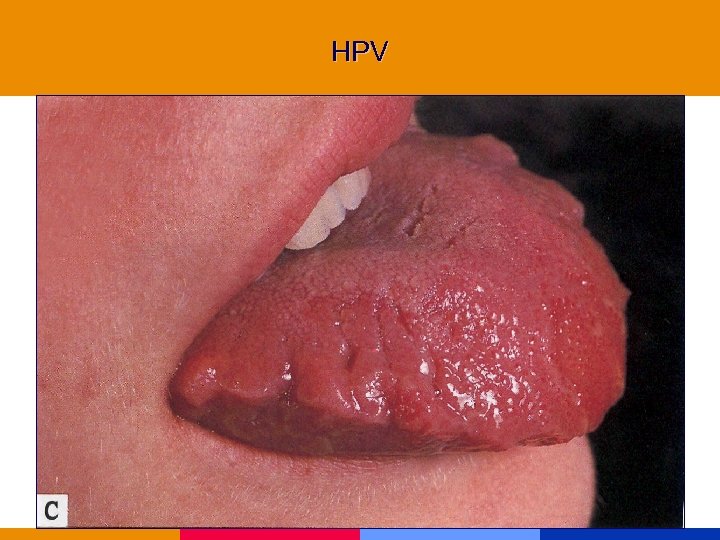

HPV

HPV